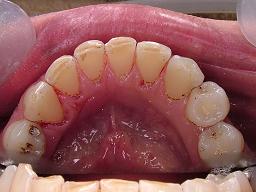

エアーフローによるクリーニングです。

初診当日、約1時間かかりましたがここまでキレイになりました。

エアーフローはほう酸の粉末をJETで歯面に当てステインを除去します。

ブラシの入らない隙間の汚れも取れ、かつ歯は傷めないスグレ物です。

エアフロ―(着色汚れ除去)の症例